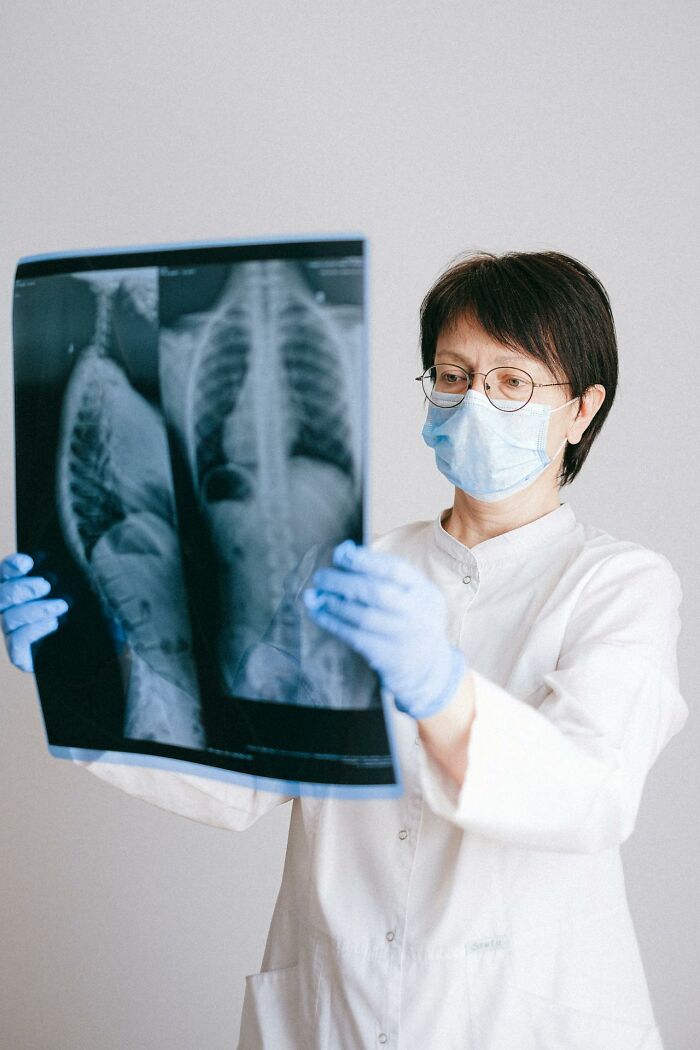

My dad was itching for months and the doctors were giving him meds for itching which didn’t help. Finally we got to an allergist who looked at his prior labs and told us to go back to his primary care dr and request a chest xray and come back to see him. Well the dr couldn’t get the xray approved even though my father was a smoker for 50 years. When we went back to the allergist, he told us there is an xray lab in the building and to get it done now.

Walked downstairs and had the xray. Which was only 20$. The xray tech walked out with my dad and told me to call the doctor right away. Which shocked me and my dad. We went back upstairs and the allergist said he will call us after he talks to the radiologist.

The allergist called me that evening and told me my father had a large tumor and he had lung cancer.